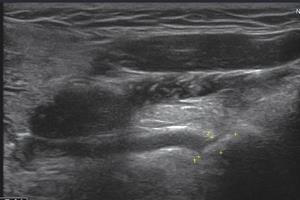

Wharton’s duct and Wharton’s dilatation

While Sonography is the preferred mode of diagnosis for salivary gland calculi, tiny calculi near salivary duct opening are hard to visualize on conventional ultrasound examination. Trans-oral sonography, however, can visualize the submandibular duct and detect the presence of small calculi, thus overcoming the limitations of transcutaneous sonography.

IO3-12 comes with E-CUBE 7, E-CUBE 9 and E-CUBE 15 and here are the images taken using a conventional linear probe and an intra-oral probe.

Conventional linear probe vs Intra-oral probe

Conventionally, the modalities used to diagnose salivary gland calculi like ultrasound, plain radiographs, sialography, CT, MR sialography, and sialoendoscopy can reveal only 20% of the calculi. Intraoral transducer, on the other hand is small and handy compared to the conventional linear transducer with a similar frequency range of about 3-12 MHz and hence it is easier to perform TOUS (Trans Oral Ultrasonography) quickly at an outpatient clinic. TOUS makes it possible to visualize oral cavity organs, such as sublingual gland, submandibular duct, tongue, lips, tonsils and soft palate, which are virtually impossible to image with conventional ultrasound. To gain a deeper understanding of the intra-oral probe application, download the research paper – Transoral Sonographic Diagnosis of Submandibular Duct Calculi_BPLAlpinion